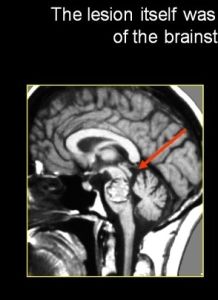

全部均行螺鏇CT掃描,其中2例行MRI檢查。腦出血3例,1例MRI表現為邊界清楚的混雜密度影,診斷為海綿狀血管瘤。本組病例均未行DSA檢查。

CM的診斷主要依據CT、MRI。高質量的CT可提供診斷依據,但敏感性和特異性不如MRI。CT平掃特徵性表現為腦實質中有邊界清楚的圖形或不規則形高密度或混雜密度灶,增強後70%~94%的病變可有輕、中度增強,典型表現為不均勻的斑點狀增強,灶周水腫一般不明顯。MRI診斷具有較高的特異性和敏感性,最典型的表現為T 2 W圖像上病灶中央有網狀或斑點狀混雜信號,病灶周圍有一均勻的環形低信號區。對CM的治療首先要考慮它是一種良性疾病,因為CM可以長時間保持靜身狀態而無任何症狀,也可因反覆出血使神經功能障礙進行性加重,故作出治療前應仔細權衡治療措施與自然病程潛在的危險,然後作出決定 。治療方式有保守治療、手術治療、放射治療。保守治療主要適用於偶然發現的無症狀病人、可用藥物控制的並發癲癇患者、病灶深在或重要皮質功能區手術風險大者、高齡或一般情況差者。放射治療用於對放射線不敏感,且不能完全防止再出血,故僅適用於治療伴有反覆出血或進行性神經功能障礙並手術又不能達到或手術風險較大的深部病灶。本組病例均行手術治療效果良好,尤以對大腦半球更佳。且能使癲癇發作消除。本組2例持續性癲癇發作者術後隨訪,未服抗癲癇藥,未發作癲癇。